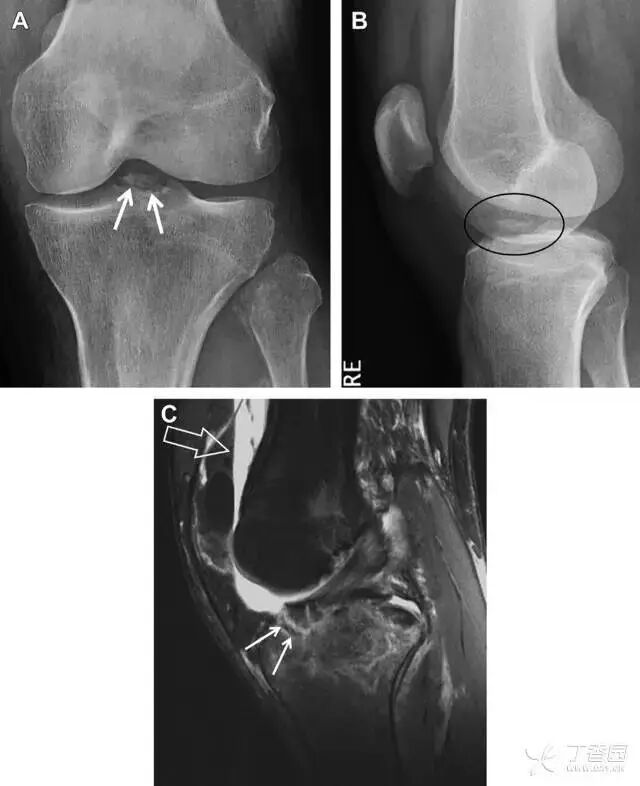

前交叉韧带胫骨髁间嵴撕脱骨折

前交叉韧带撕脱骨折常发生在胫骨髁间嵴(图 1)。这种骨折在青少年中常见,但在成年人中也并不像大家想象的那么少见。

图 1 摩托车事故患者前交叉韧带撕脱性骨折。A 正位片示胫骨髁间嵴底部骨折(箭头),注意别把这个骨折碎片错认为关节内结构。B 侧位片示胫骨上方可见一细长型骨折碎片(椭圆)。C MRI 矢状位 T2 加权像示前交叉韧带附着于撕脱的骨折碎片上(箭头),注意周围存在骨髓水肿和积脂血征(空箭头)

股骨外侧髁凹陷征(图 2)

图 2 扭伤后的股骨外侧髁凹陷征。A 侧位片示股骨外侧髁凹陷。B MRI 矢状位 T2 加权像示股骨外侧髁及胫骨后外侧骨挫伤(空箭头)。胫骨近端随着后交叉韧带撕裂发生移位,露出外侧半月板的后角(弧形箭头)